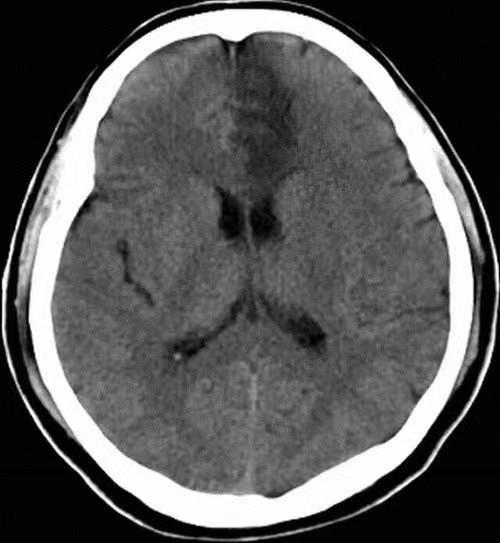

脑CT检查

脑部电脑断层扫描(CT)它是一种早期且广泛应用于临床的影像技术,被称为诊断脑出血、蛛网膜下腔出血、硬膜下出血等出血性疾病的首选。

在实际操作中,一般的CT扫描不需要特殊的准备,扫描过程很快,可以在紧急和危重的前提下立即进行。因此,脑CT已经成为急诊科常规的筛查方法,可以识别脑梗死和脑出血,并在脑梗死溶栓治疗前消除脑出血。在患者就诊过程中,一般选择先进行脑CT扫描,以消除出血性疾病的可能性,初步评估脑实质。